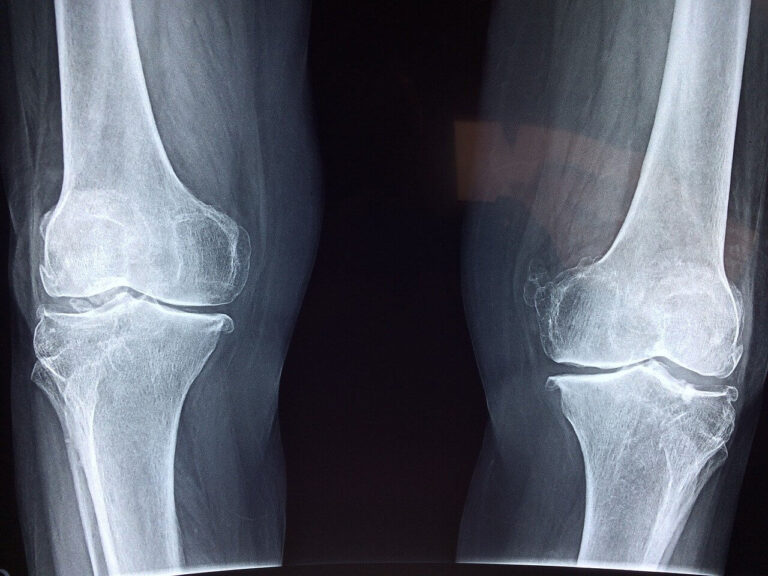

骨松症: 根据纪录,发生髋部骨折的老年人…

骨质密度下降下降,骨折的风险就会增加。…